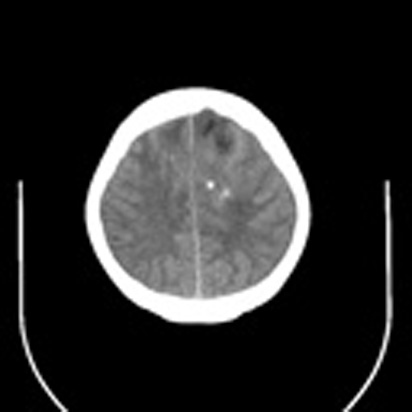

标题: CT16829:女,36,近20天偶有口眼歪斜短暂发作史,近日头痛。

近20天偶有口眼歪斜短暂发作史,近日头痛。患者先做ct发现病变后又做了mri检查,前日上传2次ct图像均未成功,今日补上。

大脑中线部位肿瘤向两侧生长,可见明显钙化影,考虑少枝胶质瘤,建议增强除外脑膜瘤

左额混杂密度肿块,经胼胝体跨越中线向右额叶生长,多考虑少支胶质细胞瘤,建议mr增强扫描,待排除血管畸形。